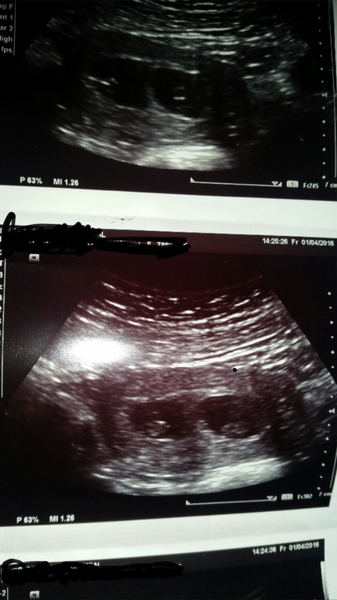

scienceteachergeek · 07/04/2016 10:43

Hi there guys. Hope you're all ok. Sorry it's taken so long for me to get back to you. The scan went well. They found TWO HEARTBEATS!